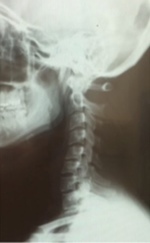

上の写真をみるとわかるように、同じ動作をしてもらいましたが動きは全く違うものになっています。

腰の上の部分の背中が固く丸まっています。

脊柱の動きの連動性がない状態になっているため、上を向く・首をねじる動作では、局所への負担が高まり痛みを繰り返しやすくあります。